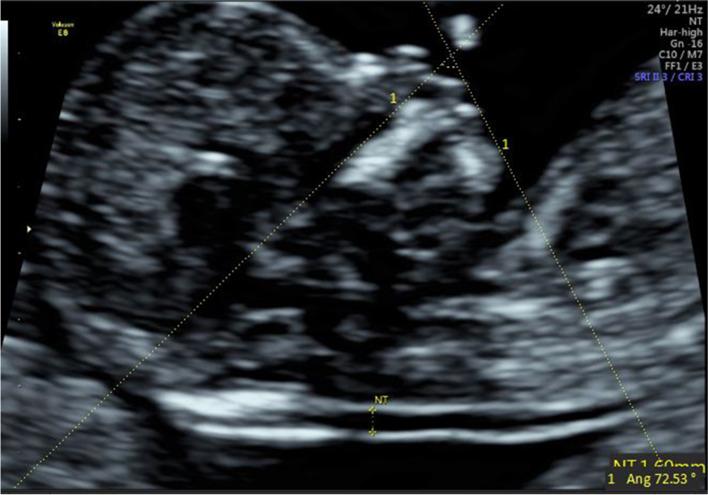

To study the correlations between facial profile markers and crown-lump length (CRL) in a Chinese population, and to evaluate the clinical value of these markers for abnormal fetuses during the first trimester (11 to 13 gestational weeks).  METHODS: The facial profile markers were as followings: inferior facial angle (IFA), maxilla-nasion-mandible (MNM) angle, facial maxillary angle (FMA), frontal space (FS) distance and profile line (PL) distance. These markers were measured in facial mid-sagittal section through ViewPoint 6 software. The diagnostic value of these markers for abnormal fetuses was assessed by receiver operating characteristic (ROC) curves.

According to the first-trimester scanning (FTS) and follow-up, 31 fetuses were enrolled in the abnormal group, including 14 cases of trisomy 21, 7 cases of trisomy 18, 10 cases with cleft lip and palate (CLP), and 1000 normal fetuses were selected. Among the normal fetuses, the IFA, FS distance and PL distance had negative correlations with CRL. The MNM angle and FMA had positive correlations with CRL. The mean IFA values for fetuses with trisomy 21 and trisomy 18 were 74.11° (standard deviation (SD) 7.48) and 69.88° (SD 7.08), respectively, which were significantly smaller than the normal fetuses (p = 0.013; p = 0.003). The mean MNM angle of fetuses with trisomy 18 and CLP were 6.98° (SD 2.61) and 9.41° (SD 2.57), respectively, which were significantly greater than the normal fetuses (p = 0.005; p < 0.001). The mean FMA values of trisomy 18 fetuses were 63.95° (SD 4.77), which was significantly smaller than the normal fetuses (p < 0.001). The mean FS distance of CLP fetuses was -0.22 mm (SD 1.38), which was significantly smaller than the normal fetuses (p < 0.001). The mean PL distance of trisomy 21, trisomy 18 and CLP fetuses were 2.89 mm (SD 0.41), 2.91 mm (SD 0.56) and 2.71 mm (SD 0.37), respectively. The difference with the normal fetuses had no statistical significance (p = 0.56; p = 0.607; p = 0.54).

面部轮廓标志如下:下面部角(IFA)、上颌-鼻根-下颌(MNM)角、面上部角(FMA)、额面间距(FS)和轮廓线(PL)距离。通过 ViewPoint 6 软件在面部正中矢状面测量这些标志。通过受试者工作特征(ROC)曲线评估这些标志对异常胎儿的诊断价值。

根据孕早期扫描(FTS)和随访,31 例胎儿被纳入异常组,包括 14 例 21 三体,7 例 18 三体,10 例唇腭裂(CLP),1000 例正常胎儿。在正常胎儿中,IFA、FS 距离和 PL 距离与 CRL 呈负相关。MNM 角和 FMA 与 CRL 呈正相关。21 三体和 18 三体胎儿的 IFA 平均值分别为 74.11°(标准差(SD)7.48)和 69.88°(SD 7.08),显著小于正常胎儿(p=0.013;p=0.003)。18 三体和 CLP 胎儿的 MNM 角平均值分别为 6.98°(SD 2.61)和 9.41°(SD 2.57),显著大于正常胎儿(p=0.005;p<0.001)。18 三体胎儿的 FMA 平均值为 63.95°(SD 4.77),显著小于正常胎儿(p<0.001)。CLP 胎儿的 FS 距离平均值为-0.22mm(SD 1.38),显著小于正常胎儿(p<0.001)。21 三体、18 三体和 CLP 胎儿的 PL 距离平均值分别为 2.89mm(SD 0.41)、2.91mm(SD 0.56)和 2.71mm(SD 0.37),与正常胎儿相比差异无统计学意义(p=0.56;p=0.607;p=0.54)。